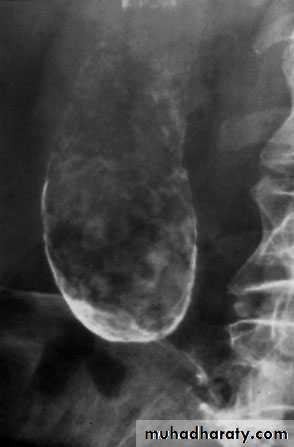

RADIOLOGICAL INVESTIGATION OF THEBILIARY TRACTPlain radiographA plain radiograph of the gall bladder will show radio-opaquegallstones in 10% of patients with gallstones . Rarely,the centre of a stone may contain radiolucent gas ‘Mercedes-Benz’ sign in the A plain X-ray may also show the rare cases of calcification ofthe gall bladder, a so called ‘porcelain’ gall bladder .The importance of this appearance is an association with carcinomain up to 25% of patients. Gas may be seen in the wall of the gall bladder(emphysematous cholecystitis). Gas in the biliary tree may be seen after endoscopic sphincterotomy or surgical anastomosis Oral cholecystography and intravenouscholangiographyOral and intravenous cholecystography are of historical interest only .